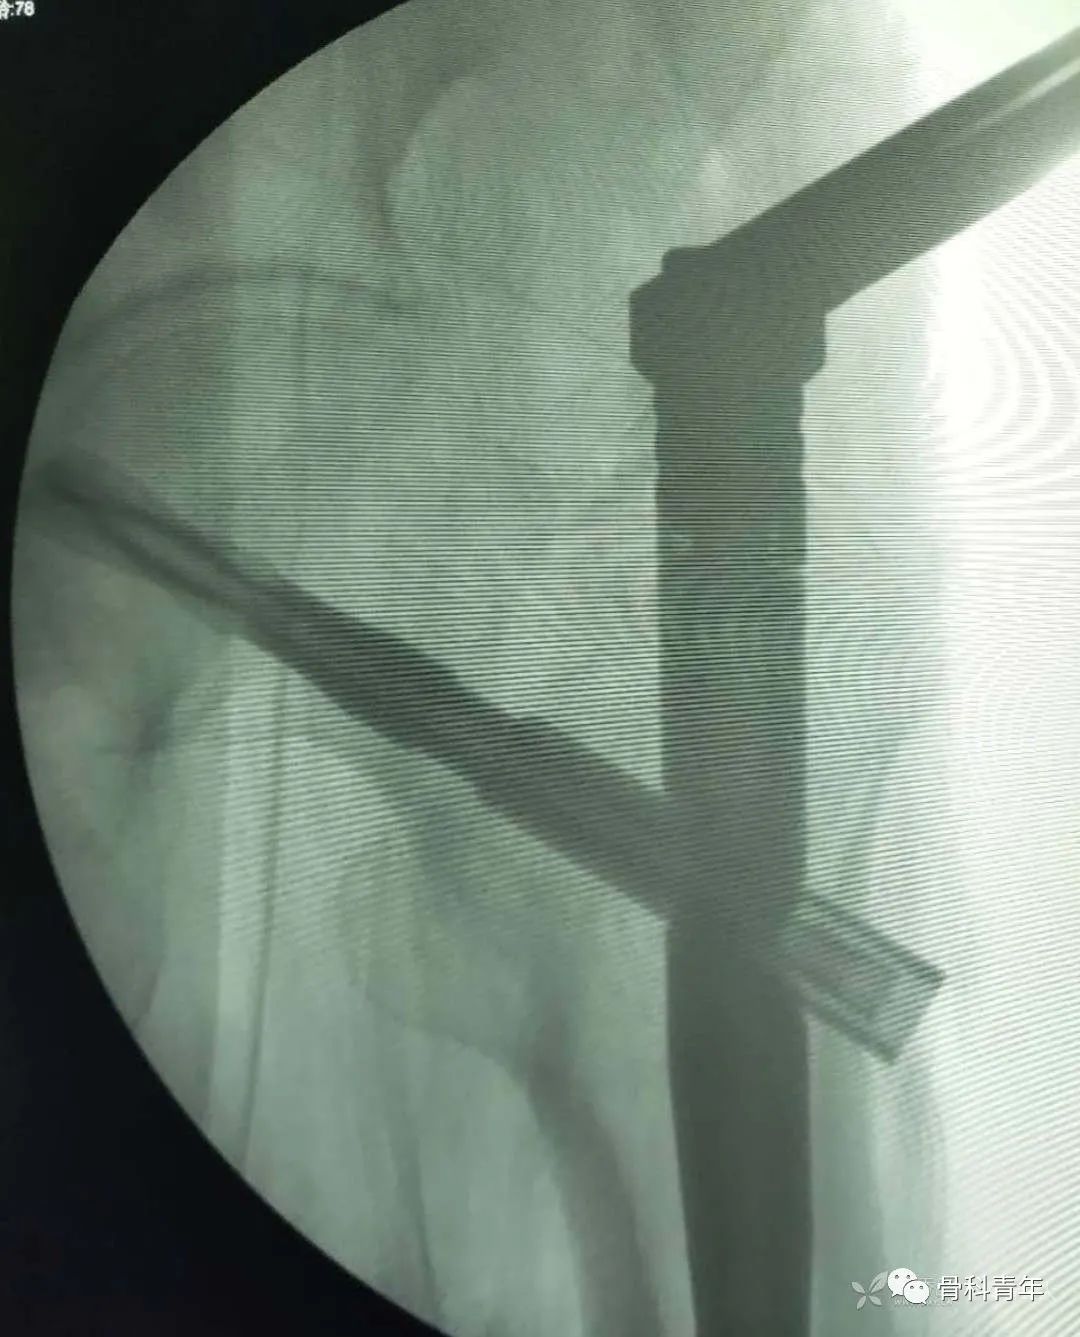

我的解决办法是——内移进针点:

进针点由大转子尖向内移(内侧缘斜坡上):

主钉的位置就很标准,不会出现“撑开效应”(在骨折端进钉):

手术不同于假骨操作,切口周围软组织往往产生阻挡效应,将套筒往外侧推,也是扩髓骨道外移的原因。当患者腹部脂肪很多时,这种软组织阻挡效应会更加明显

解决办法:1.胶布拉开腹部脂肪。2.内移进针点,同时上移切口,换用弯头手柄,减少软组织阻挡效应。